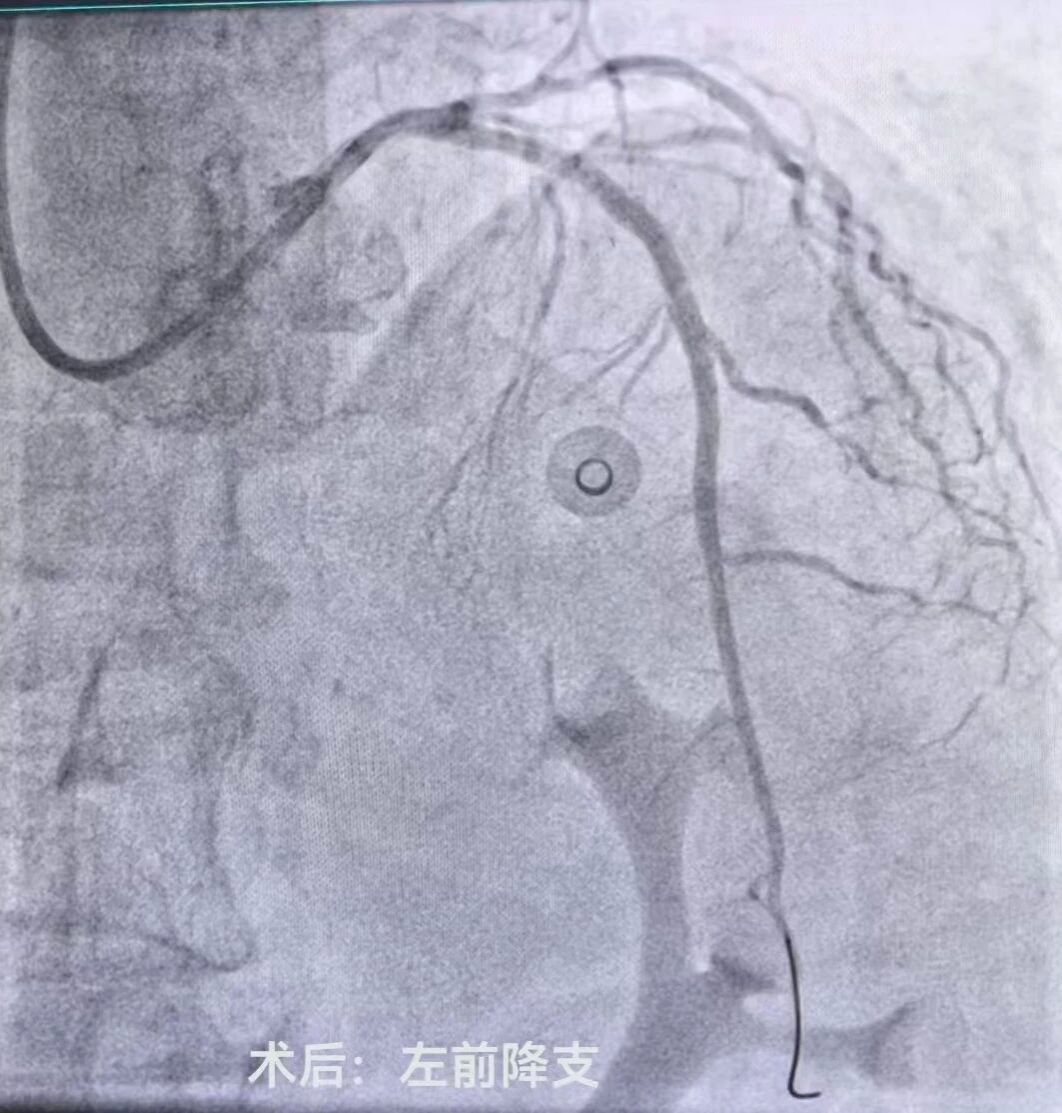

介入室内,医护团队严格遵循标准化操作流程,消毒、穿刺、造影等步骤一气呵成。冠状动脉造影显示心脏三支血管均有严重狭窄,其中两根主要血管均有95%以上的堵塞,患者已出现心力衰竭表现,生命危在旦夕,只有一次性处理两处严重狭窄病变才能为患者带来生的希望。刘晓建主任带领的介入团队凭借丰富的临床经验和精湛的介入技术预判手术风险,勇担重任,术中认真仔细操作,快速高效的同时完成了左前降支(LAD)、右冠状动脉(RCA)球囊扩张及支架植入术。随着支架成功释放,闭塞的血管瞬间恢复通畅,心肌供血得以重建,患者胸闷、胸痛症状较前明显缓解,生命体征逐渐平稳。

术前术后对比